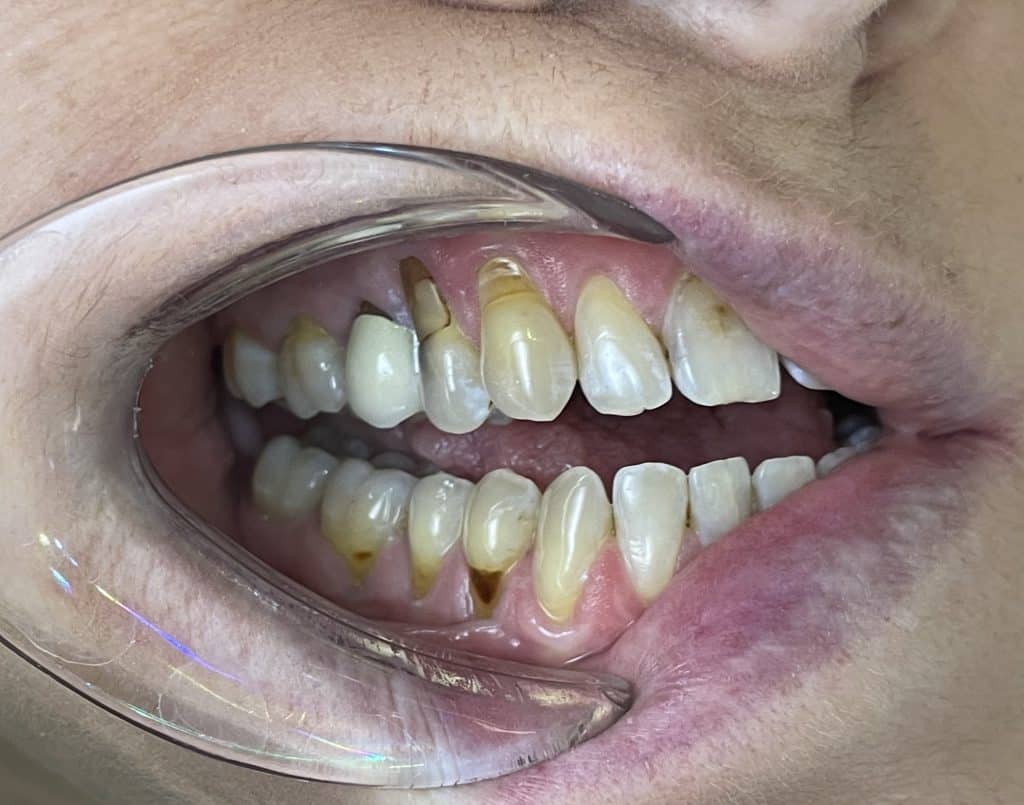

We report the case of a female patient, approximately 55 years of age, with multiple gingival recessions and abfraction lesions.

multiple gingival recessions and abfraction lesions in the first and forth quadrants

pre operative photo 4° quadrant